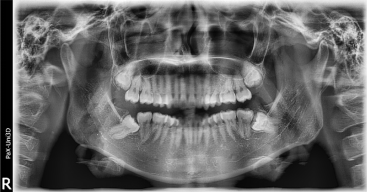

一、智齿个头可大可小。通常智齿和第一磨牙、第二磨牙的大小相当或者更小,总体与自身牙列比例协调。有时会呈现过小牙,牙冠短小圆滑,牙根锥形,实则为一种牙齿畸形的表现。

二、萌出和生长的数量可多可少。临床上最常见到的是双侧下颌智齿萌出和发育,上颌可有可无,拍片发现上颌先天缺如的情况不在少数。当然也有四个智齿全部先天缺失、或者某一侧智齿先天缺失的情况。所以智齿生长的数量是0-4颗不等。

三、智齿位置可高可低。先天基因决定的宽下颌,以及后天养成的大力咀嚼习惯(例如喜硬食),有可能获得一口32颗排列整齐的牙齿。但目前看来,人群中因智齿阻生造成的牙列拥挤、前牙龋坏、颌骨或淋巴炎症等比比皆是。阻生,就是各种原因导致的生长方向、生长路径受阻,如低位、斜位、水平位甚至倒立位,不能到达正常的咬合平面,从而无法行使应有的咀嚼功能。智齿显然已成为口腔健康的一大潜在杀手。